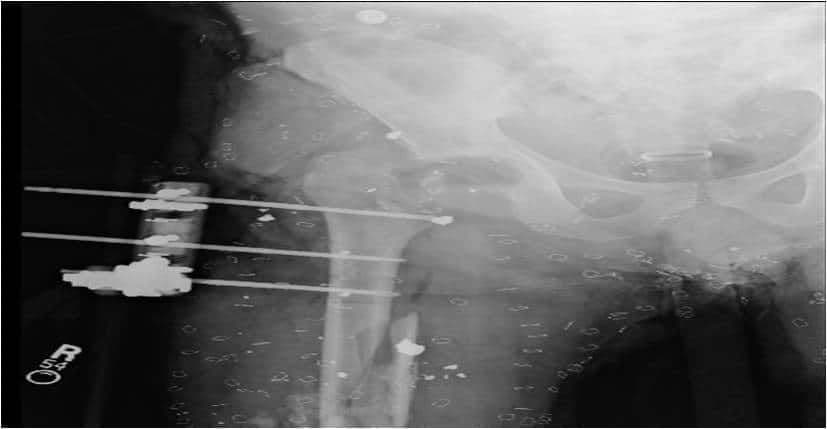

2. Уникайте встановлення штифта занадто близько до місця перелому (штифти всередині самого перелому зменшать здатність зовнішнього фіксатора підтримувати стабільність перелому) (зобр. 2 і зобр. 3. Рентгенологічний знімок цієї гомілки у прямій проекції передбачає адекватне розміщення зовнішнього фіксатора, проте на бічному знімку видно, що проксимальний штифт дистальної групи штифтів знаходиться всередині перелому).

Зобр. 2

Зобр. 3